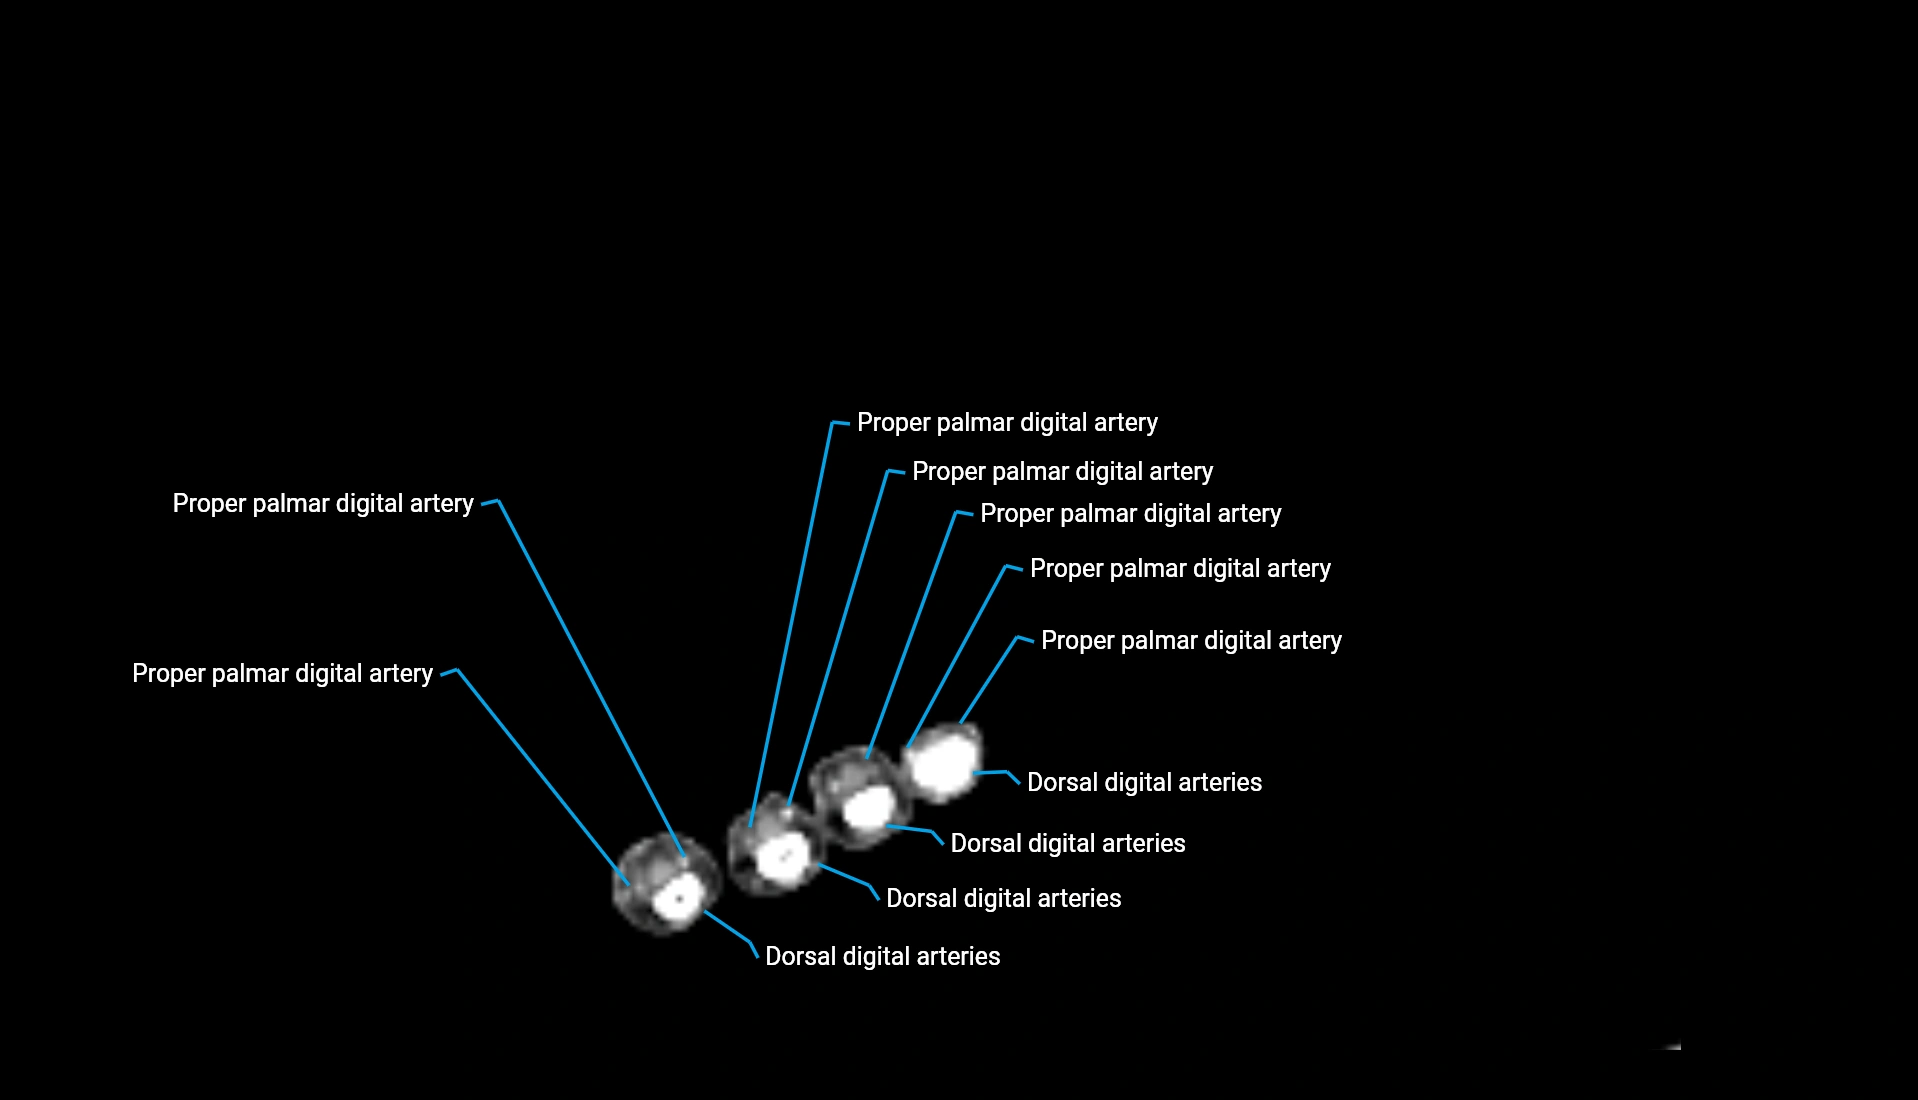

CT Appearance

Non-Contrast CT:

• Cortex: High-density, sharply defined

• Subchondral bone: Dense cancellous matrix

• Articular surface: Smooth concave contour articulating with the capitellum

• Excellent for evaluating bone integrity, alignment, and subtle fractures